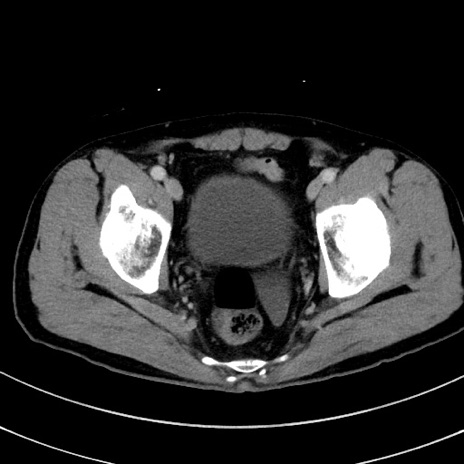

症例8(横断像)

【症例】 60歳代男性

【主訴】 黒色吐物

【現病歴】 4日前から嘔気自覚、2日前の朝食後にも嘔気あり、自分で手で嘔吐反射起こし嘔吐したところ血が混ざっていたため受診。

【既往歴】 5年前汎発性腹膜炎を伴う急性虫垂炎で手術、高血圧、前立腺肥大症、高脂血症

【身体所見】 腹部正中に手術癩痕あり 腹部平坦・軟圧痛なし膨満感あり

【データ】WBC 8400、CRP 4.54